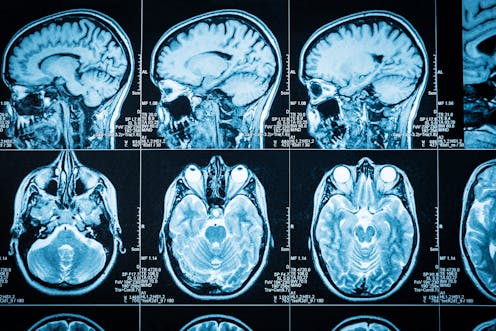

In a UK-based study released as a pre-print online in June, researchers compared brain images taken of people before and after exposure to COVID. They showed parts of the limbic system had decreased in size compared to people not infected. This could signal a future vulnerability to brain diseases and may play a role in the emergence of long-COVID symptoms.